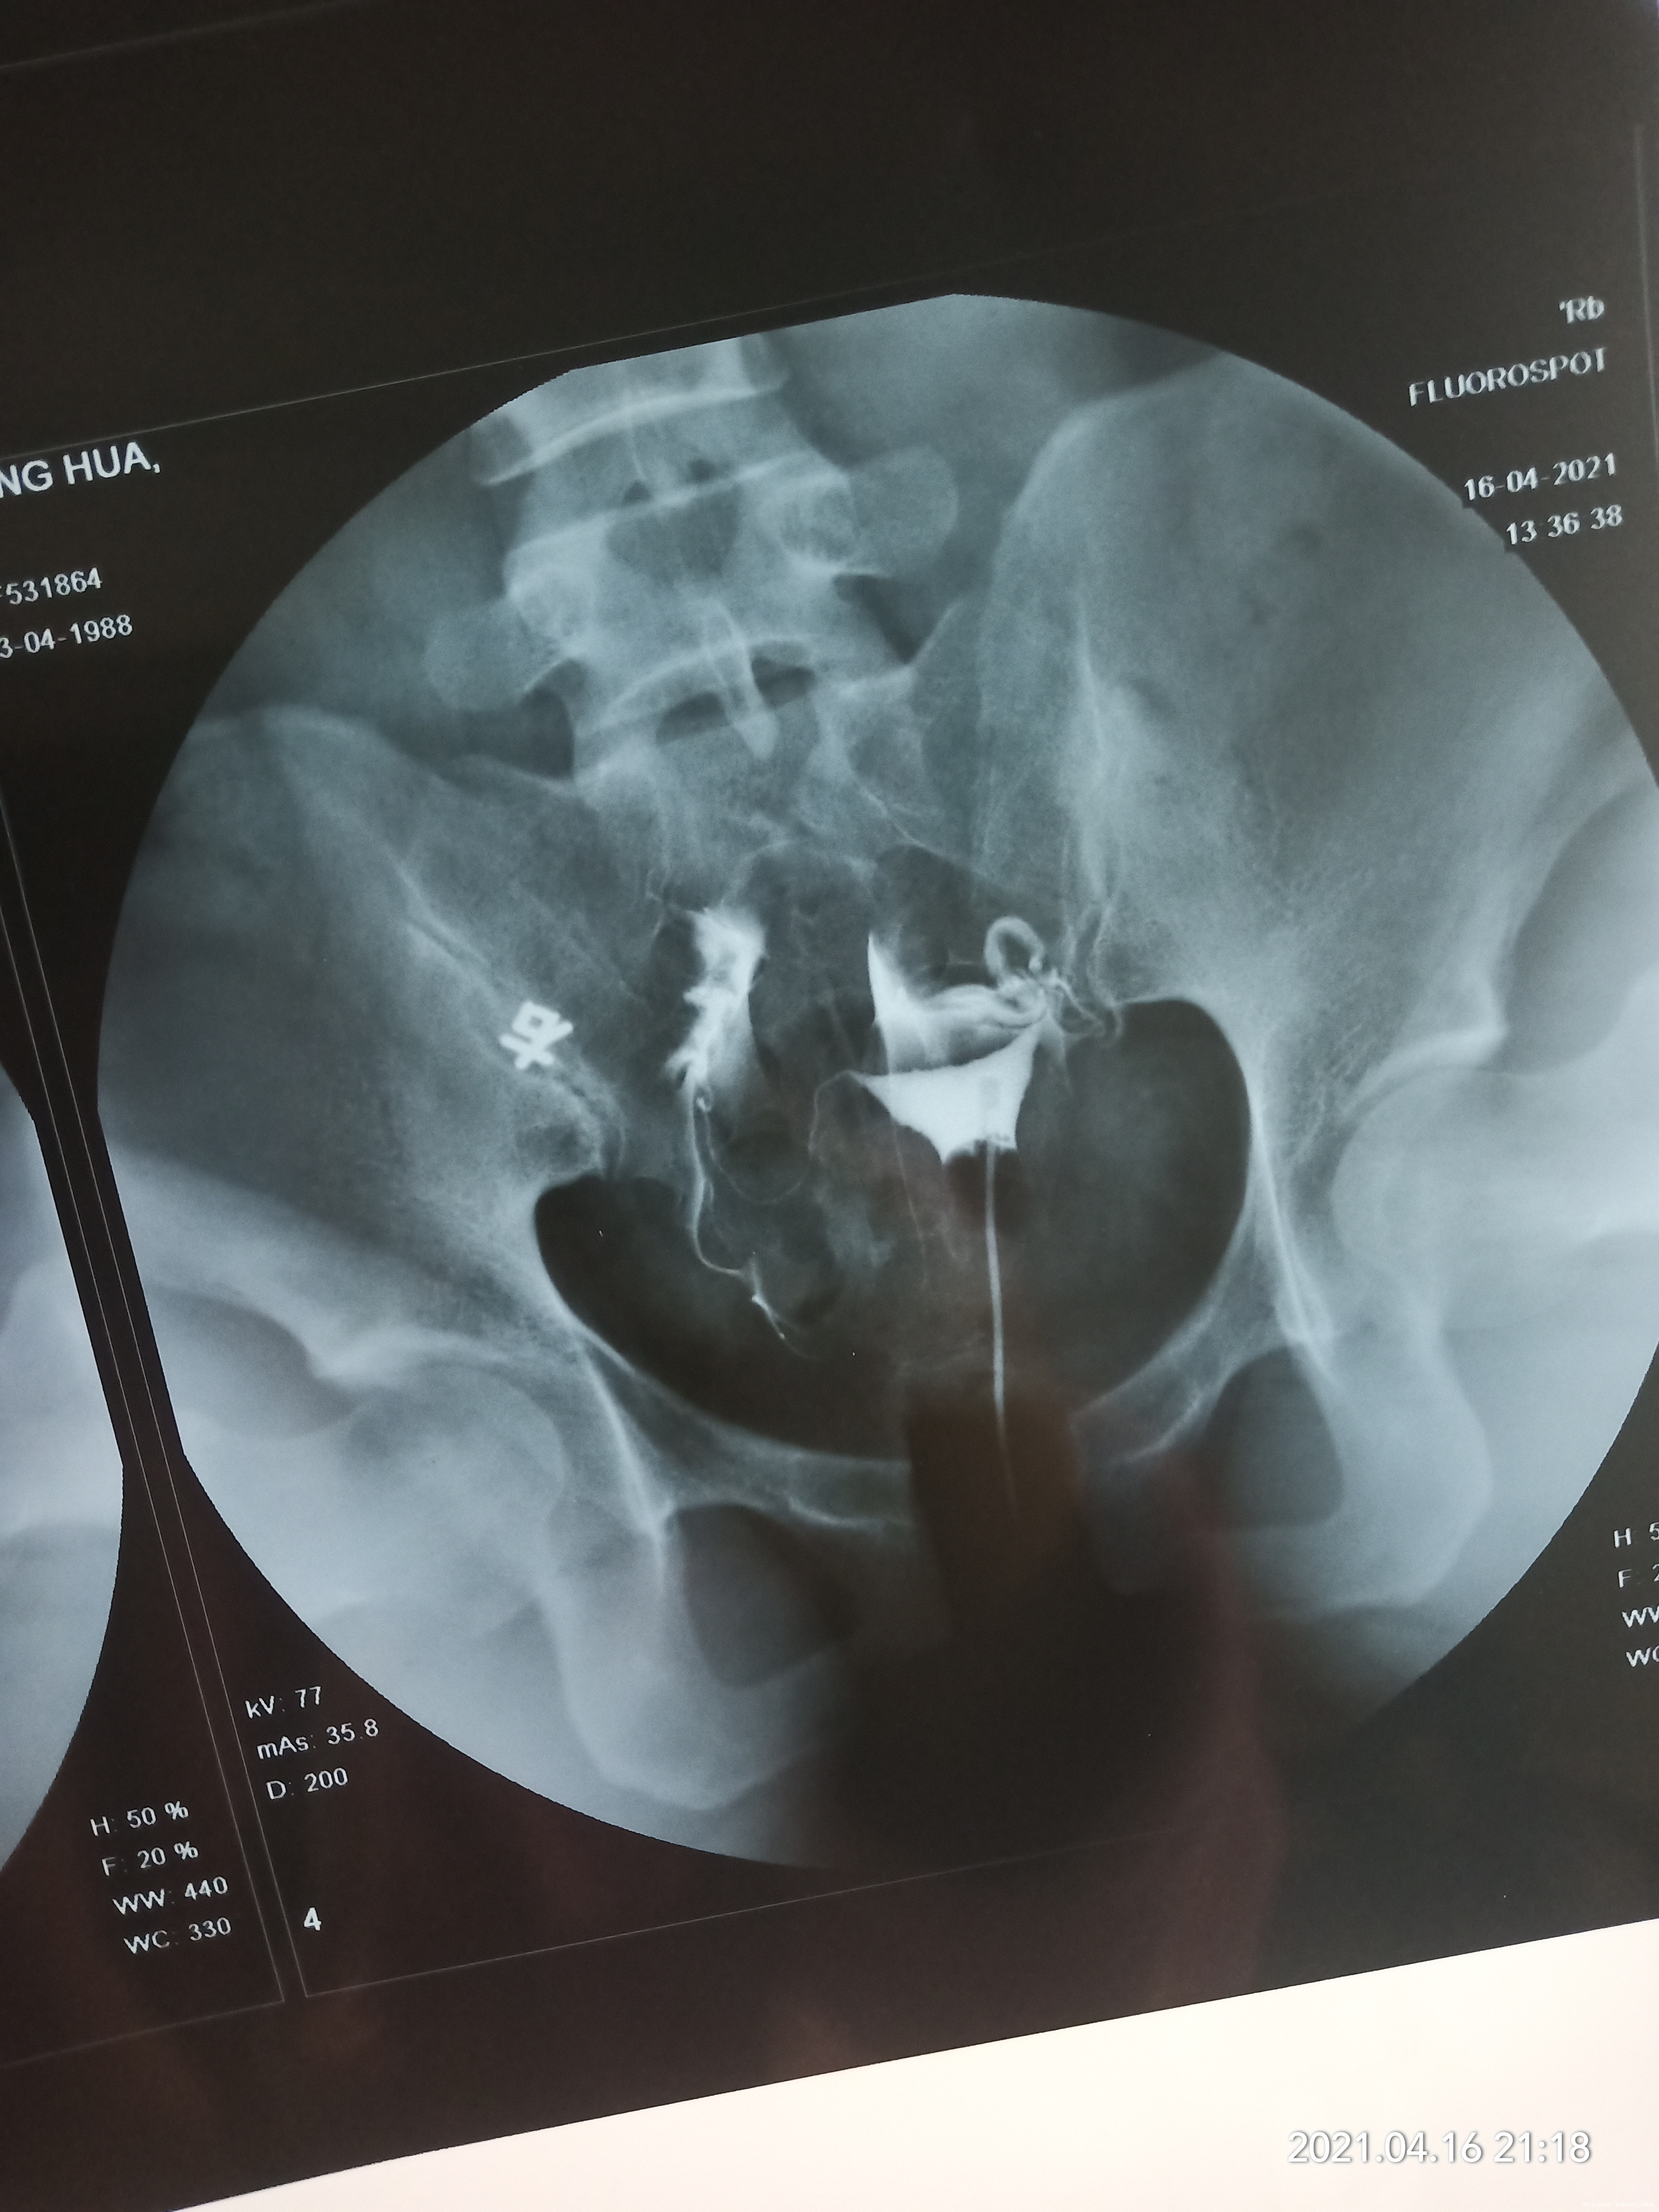

你好!从造影片子来看左侧输卵管扭曲,不通;右侧输卵管远端造影剂堆积,盆腔造影剂弥散欠佳!建议腹腔镜处理输卵管或者直接试管婴儿助孕!祝您早日好孕!

你好,右侧输卵管盆腔弥散差,考虑有伞断黏连,左侧输卵管走形迂曲上举。建议宫腹腔镜联合。或者备孕3个月不怀孕可以试管。

从检查结果来看,右侧输卵管盆腔弥散差,伞断黏连,左侧输卵管走形迂曲上举。结合你的年龄建议宫腹腔镜联合。或者备孕3个月不怀孕直接做试管移植,祝早日好孕!